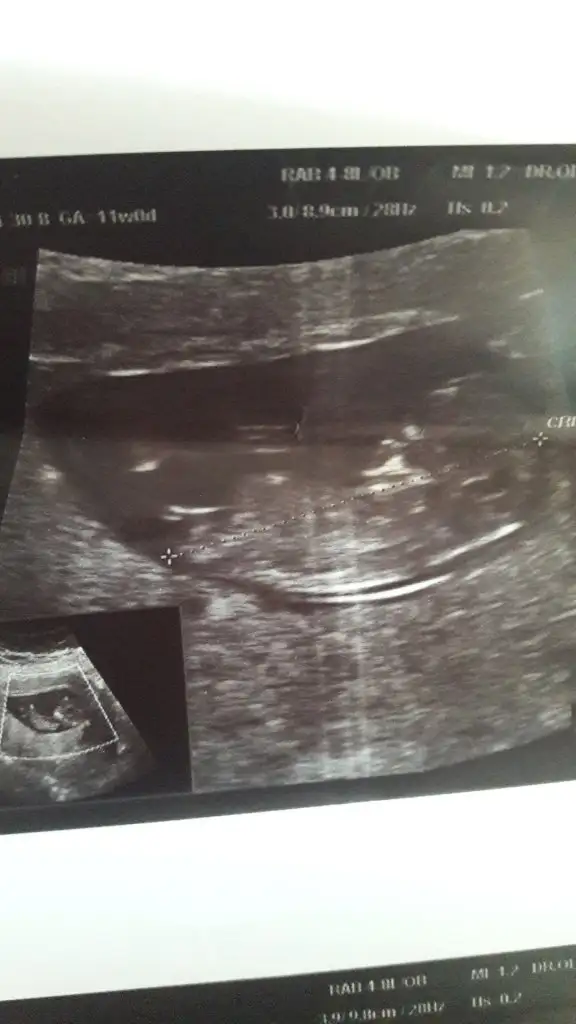

14+3 tahminde bulunurmusunuz🤦‍♂️

• USER_SCOPED_TEMP_DATA_MSGR_PHOTO_FOR_UPLOAD_1619699855146_6793513581238554568.webp

USER_SCOPED_TEMP_DATA_MSGR_PHOTO_FOR_UPLOAD_1619699855146_6793513581238554568.webp

16,7 KB · Görüntüleme: 69